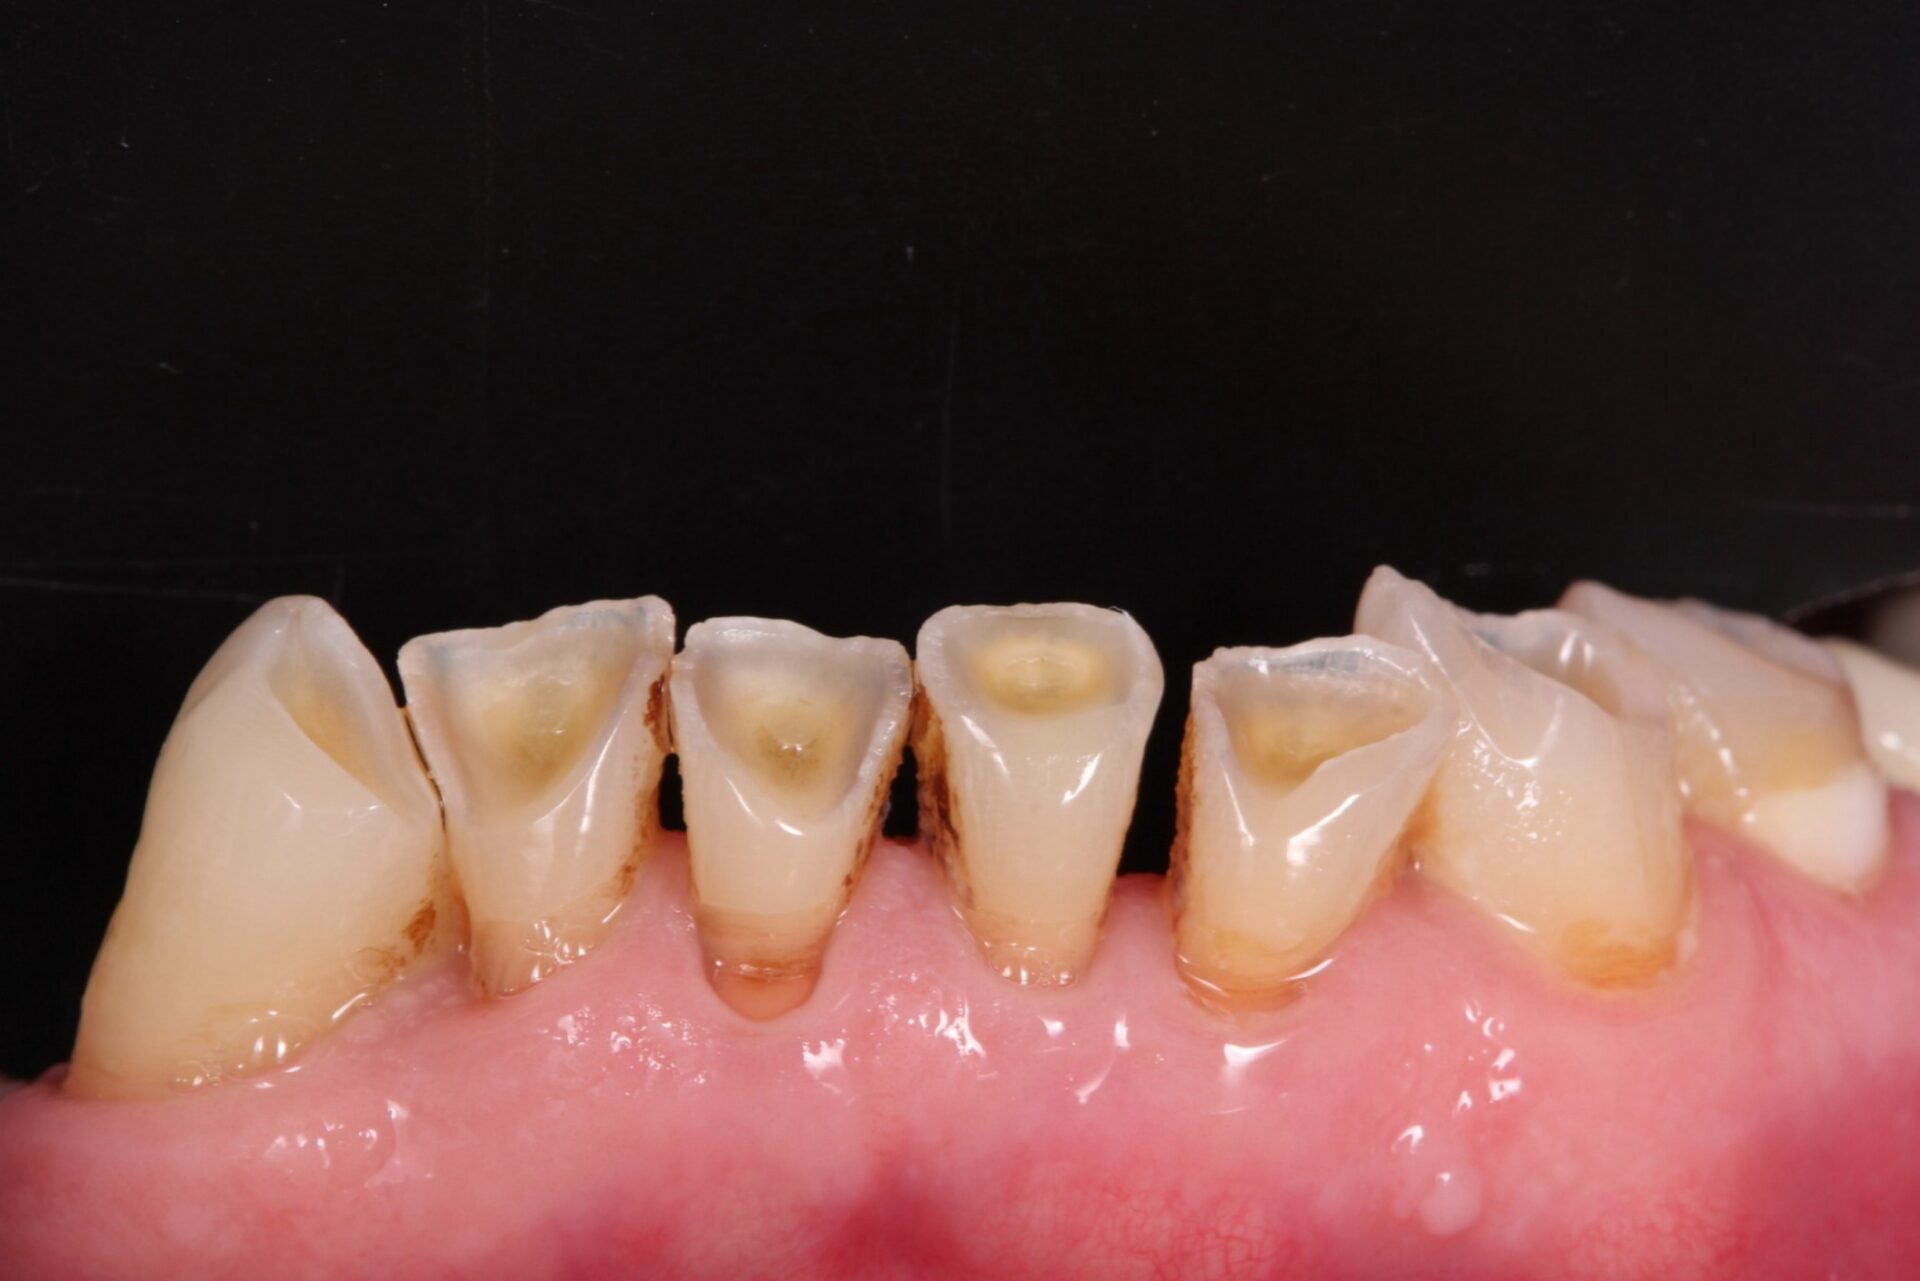

Ejemplo de un caso en paciente con erosiones:

- Antes – Inferior